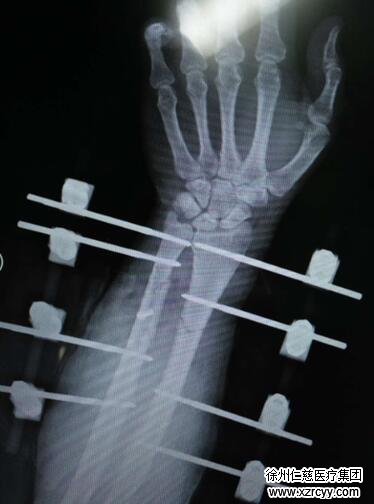

各项检查完毕后,手术室内,由于右臂异常肿胀,小张的右前臂切开后创面就像熟透的西瓜炸裂一样难以缝合。“我们首先对他进行了切开减压与清创,然后修复了损坏的血管与神经,因为患者右尺桡骨骨折,我们复位后给患者进行了外固定支架固定。患者后期还需皮瓣修复创面,他的前臂皮肤软组织缺损面积较大。”黎医生说。

1月3日,黎医生团队为小张实施了右前臂清创股前外侧游离皮瓣修复术,取小张大腿外侧皮肤进行手臂的修补,因为大腿外侧供区隐蔽性好,且大腿皮肤与前臂皮肤相近,手术整整进行了5小时,股前外侧游离皮瓣难度较大,需要手术者有高超的微血管吻合技术与丰富的手术经验。